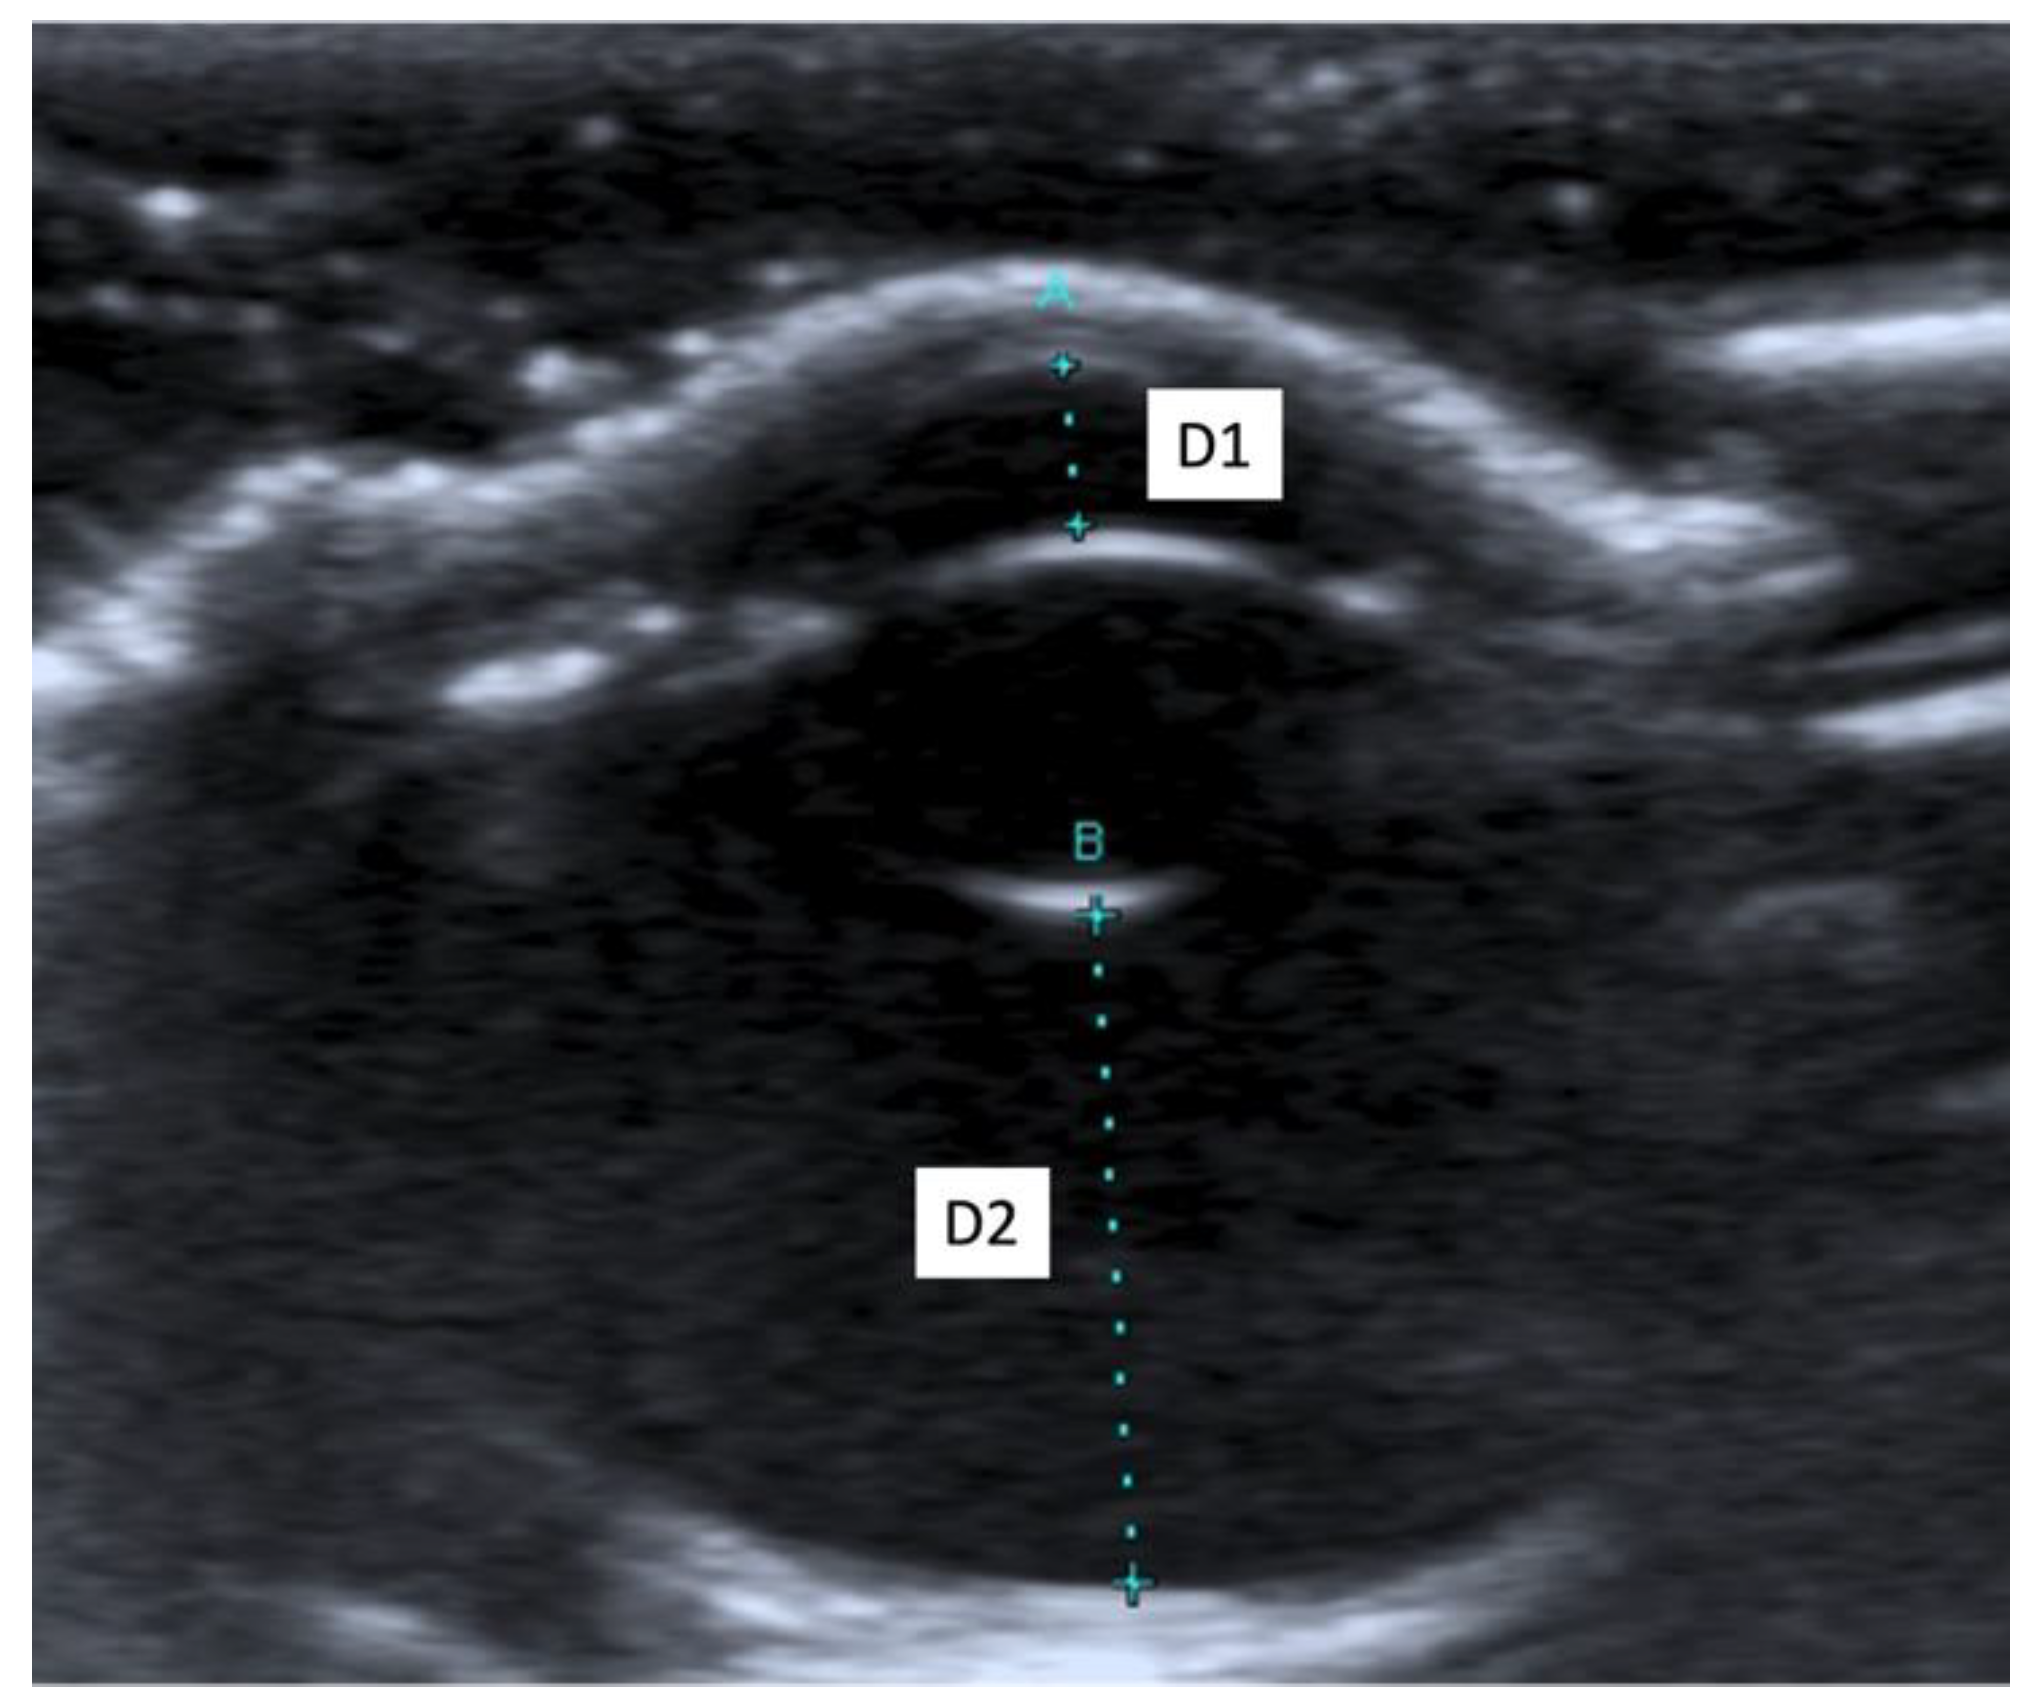

2.4. Ultrasound Biometric Measurements

3.2. Ultrasound Biometric Measurements

| (a) | |||||||||||||||

| Both breeds | OS 1 (n 3 = 27) | OD 2 (n 3 = 27) | Mean OS 1 + Mean OD 2 | ||||||||||||

| D1 5 | D2 6 | D3 7 | D4 8 | D5 9 | D1 5 | D2 6 | D3 7 | D4 8 | D5 9 | D1 5 | D2 6 | D3 7 | D4 8 | D5 9 | |

| Mean (mm) | 1.68 | 7.41 | 4.29 | 15.09 | 18.01 | 1.66 | 7.48 | 4.32 | 15.16 | 18.07 | 1.67 | 7.44 | 4.30 | 15.12 | 18.04 |

| SD 4 (mm) | 0.16 | 0.18 | 0.11 | 0.44 | 0.49 | 0.16 | 0.20 | 0.17 | 0.37 | 0.49 | 0.12 | 0.17 | 0.12 | 0.37 | 0.43 |

| Median (mm) | 1.70 | 7.40 | 4.30 | 15.20 | 18.10 | 1.70 | 7.50 | 4.30 | 15.20 | 18.00 | 1.65 | 7.45 | 4.30 | 15.05 | 18.05 |

| Maximum (mm) | 2.10 | 7.70 | 4.50 | 15.80 | 18.80 | 1.90 | 7.80 | 4.70 | 15.90 | 18.90 | 1.95 | 7.75 | 4.55 | 15.80 | 18.85 |

| Minimum (mm) | 1.40 | 7.00 | 4.10 | 14.30 | 16.80 | 1.30 | 7.10 | 4.10 | 14.60 | 17.30 | 1.45 | 7.05 | 4.10 | 14.50 | 17.25 |